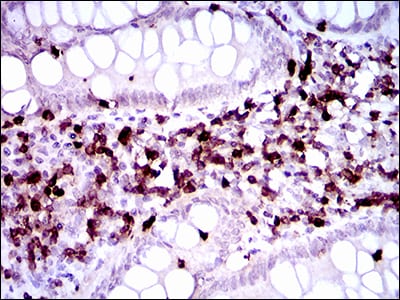

分类: 科研抗体货号: 30486P别名: ERBB; HER1; mENA; ERBB1; PIG61应用: WB,IHC,FCM反应种属: Human

分类: 科研抗体货号: 30486A别名: ERBB; HER1; mENA; ERBB1; PIG61应用: WB,IHC,FCM反应种属: Human